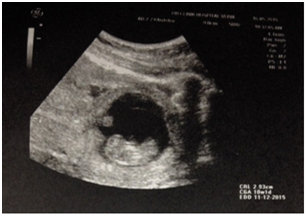

Because of the equivocal findings of the ultrasound an abdominopelvic CT scan with contrast was performed which revealed a large amount of free intraperitoneal fluid and identified with certainty that the source of bleeding was the lower pelvis (Figure 3 & Figure 4).

Figure 4 1CT scan with contrast-pelvic section.